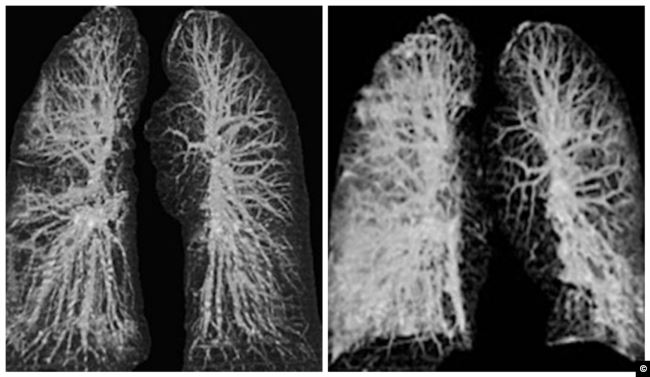

نشرت صحيفة" ديلي ميل" البريطانية مجموعة صور وصفتها بالمروعة لتدمير فيروس كورونا المستجد، رئات شخصين في الستينات من العمر من مدينة ووهان الصينية، كانا في رحلة إلى إيطاليا.

وكشفت صور الأشعة السينية وصور الأشعة المقطعية كيف دمر الفيروس  وجهازهما التنفسي بطريقة مماثلة  لتأثير فيروسي سارس وميرس وقد أظهرت الأشعة المقطعية للمريضين تورم الأنسجة الرخوة في الرئة، وقد امتلأت بالصديد والدم، أو الماء.